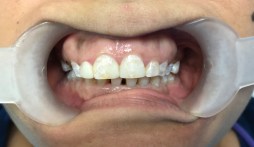

#8 e.max crown